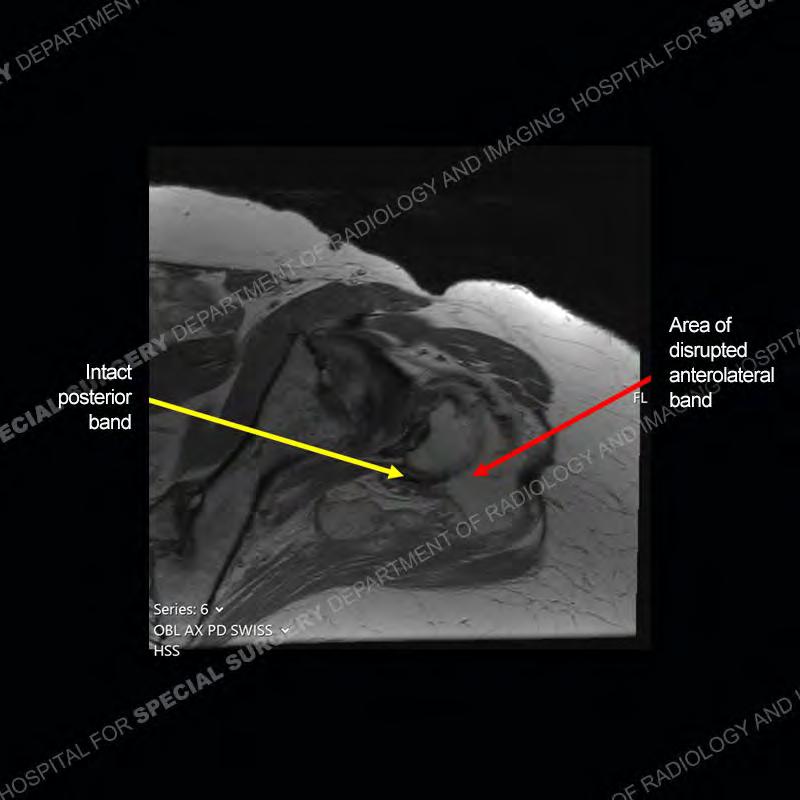

The radiograph is not particularly contributory in this case. The MRI demonstrates markedly abnormal architecture of the gluteus minimus and anterolateral band of the gluteus medius. Portions of the tendons are high signal, portions are highly attenuated, and portions are disrupted. A large, complex fluid collection is present in the adjacent soft tissue.

Not as much of a diagnostic dilemma as many of the other cases shown but just a nice example of the pathology seen of the gluteal tendons and a cause of trochanteric pain. Although, frequently thought of in isolation, trochanteric bursitis or bursal thickening is much more commonly a reactive change to underlying pathology of the subjacent gluteal tendons. The gluteus medius is divided into a posterior band and an anterolateral band. Tendinosis and partial tearing very commonly will involve the gluteus minimus and especially the more posterior fibers and then propagate into the anterior lateral band of the gluteus medius. Involvement of the posterior band of the medius is much less common and engenders a marked degree of functional impairment.